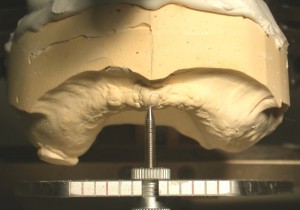

阿部晴彦先生考案の模型分析装置

阿部晴彦先生考案の模型分析装置

顎そのものがでっぱていて左右のバランスが悪い

顎そのものがでっぱていて左右のバランスが悪い